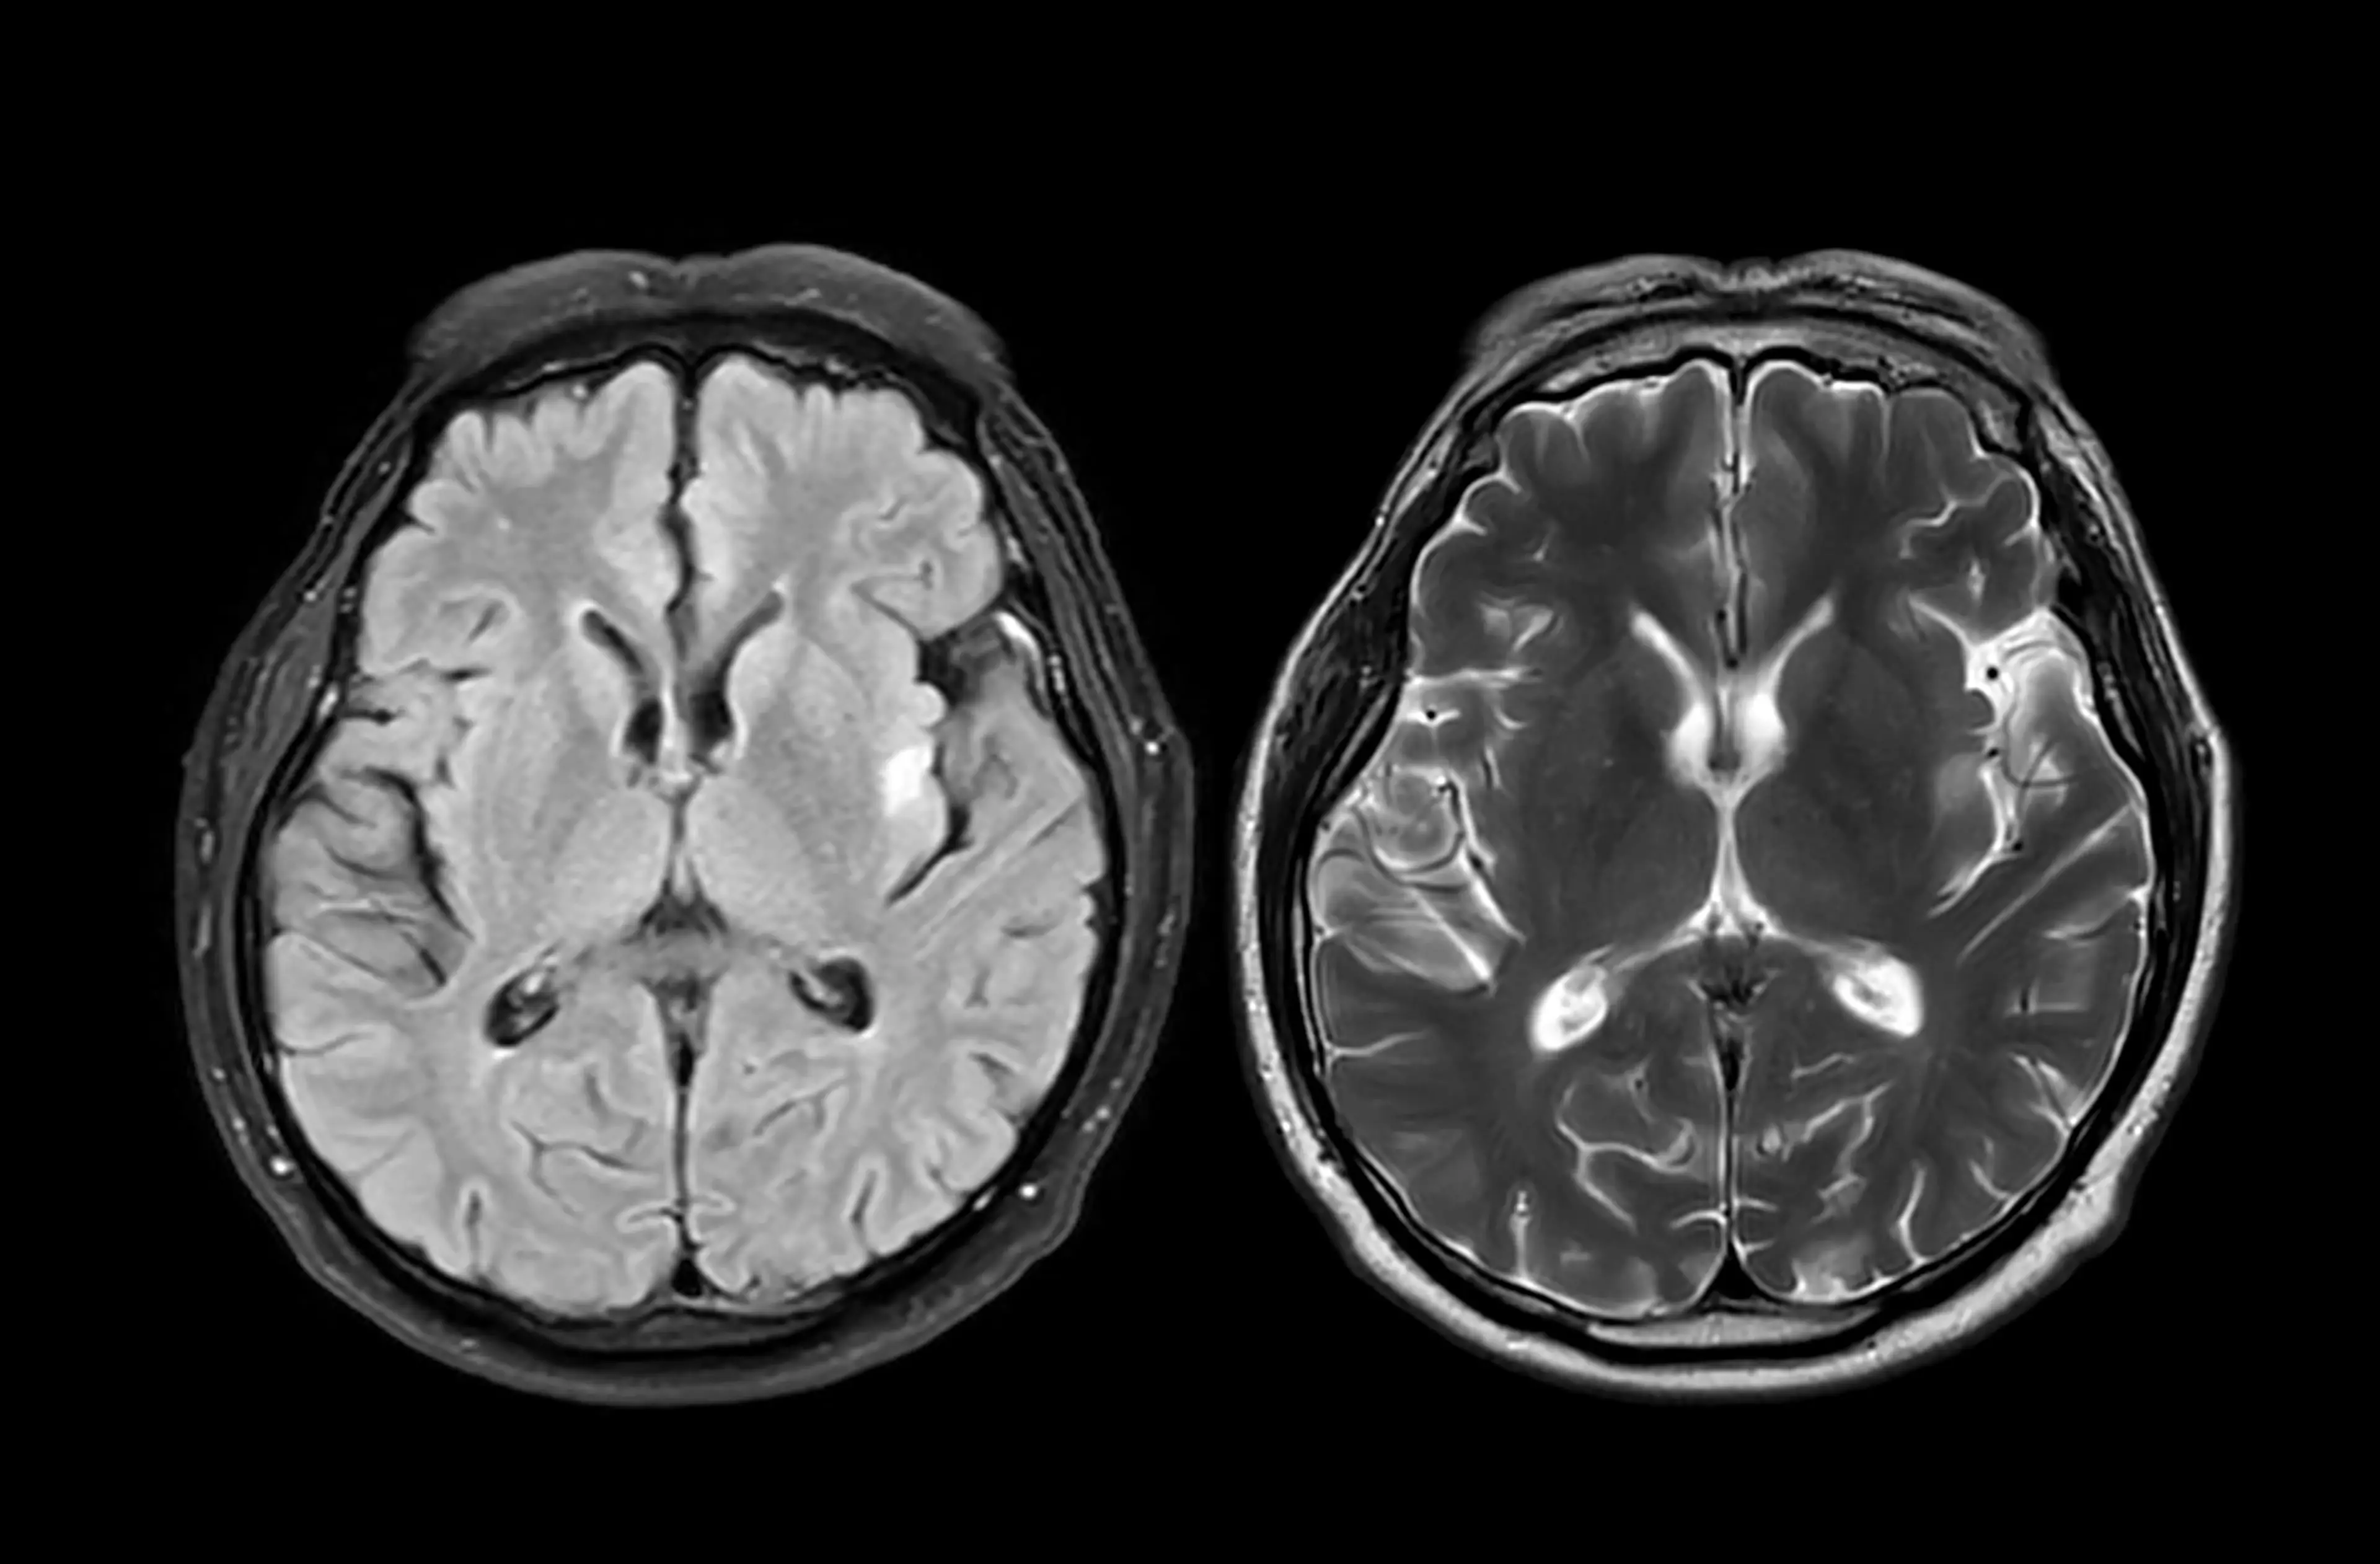

This is because dementia damages the frontal lobe and orbitofrontal cortex of the brain, which are the areas responsible for judgment, inhibition, planning, and evaluating risks.

Dementia causes atrophy of the brain's Broca's and Wernicke's areas, affecting how speech is articulated, and language is understood, which can make communication harder.